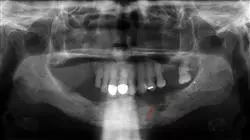

Le Infezioni Osteoarticolari in Ortopedia Pediatrica sono alte, possono comparire frequentemente in pazienti di meno di 5 anni e, sebbene nella maggior parte dei casi si tratti di bambini precedentemente sani, ci sono una serie di fattori che predispongono al loro sviluppo La sua eziologia è prevalentemente batterica e ci sono alcuni risultati clinici che dimostrano segni della sua diagnosi.

La corretta individuazione di questi segni e sintomi consente di stabilire una terapia adeguata alle esigenze del paziente e in modo precoce per evitare conseguenze o aggravanti. Negli ultimi anni, è stato dimostrato che l'uso di alcune linee guida farmacologiche contribuisce al miglioramento dei segnali rilevati. Per questo motivo, lo studio di tutti questi aspetti, dalle caratteristiche microbiologiche delle varie patologie infettive a livello muscolo-scheletrico nel paziente pediatrico fino ad affrontare altre artropatie non infettive, e la sua gestione, sarà ciò che verrà studiato in questo programma.